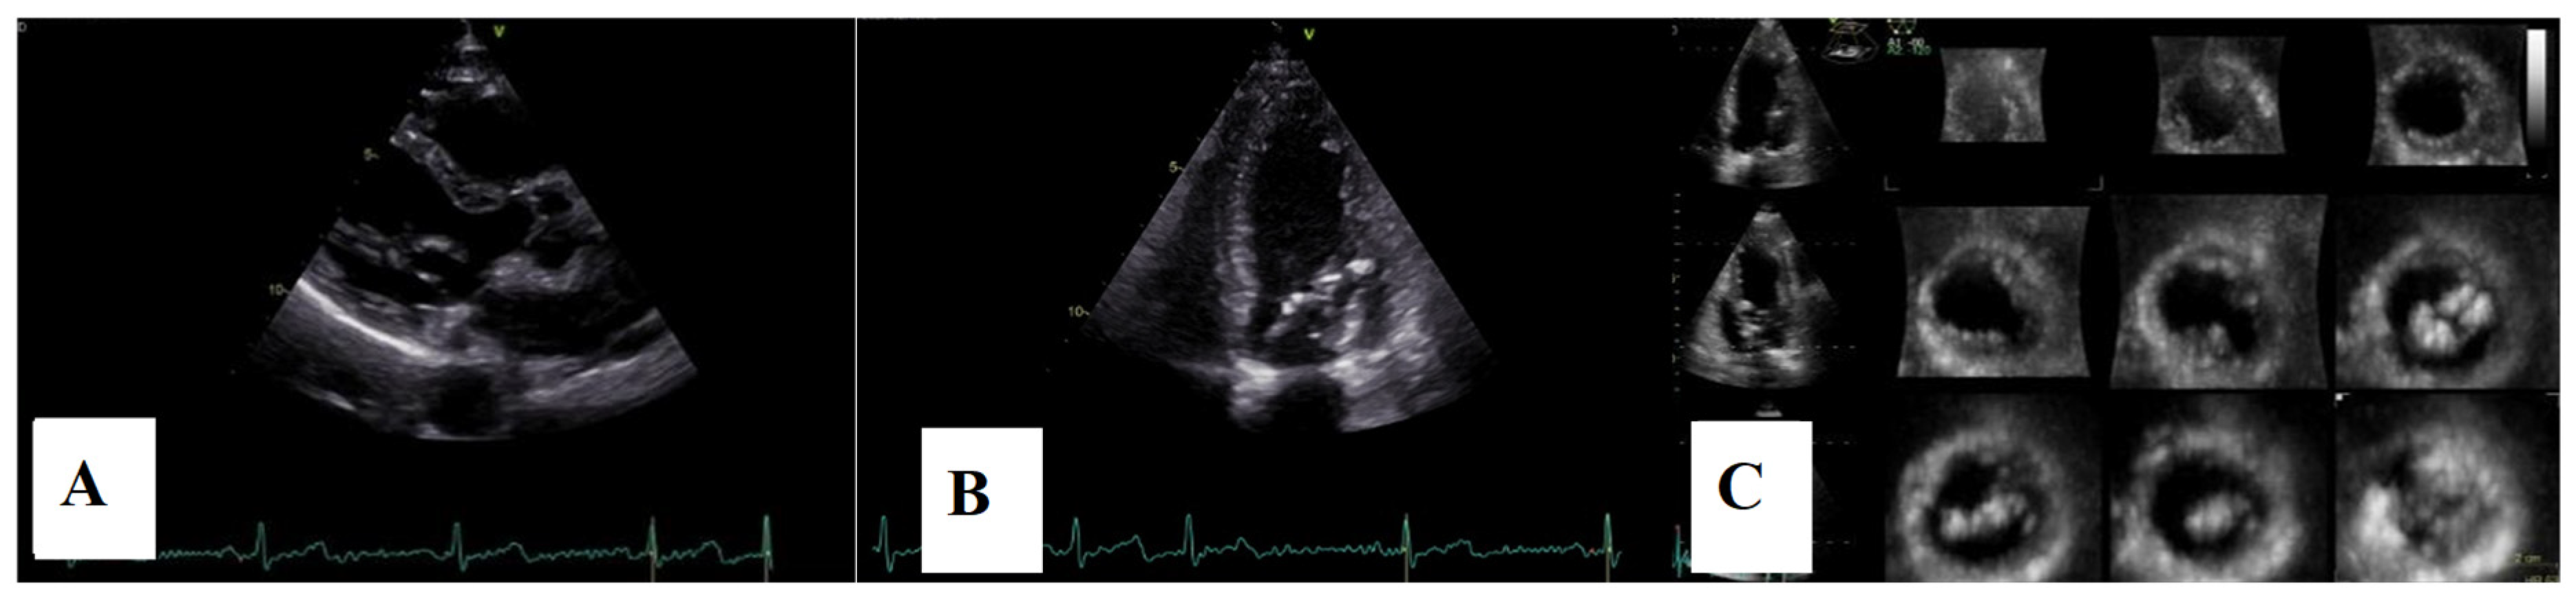

Postoperative transthoracic echocardiographic evaluation showed a left ventricle of normal size and function, a hyperechogenic mitral annulus, and hyperechogenic mitral leaflets without billowing, with only minor residual regurgitation. Additionally, two distinct groups of hyperechoic chordae were visualized at the level of the papillary muscles (Figure 10).

Figure 10.

(A)—Postoperative TTE parasternal long axis view. (B)—apical four-chamber view. (C)—3D echocardiography, 12 slices, displaying hyperecogenic mitral annulus, hyperecogenic mitral leaflets without billowing, and two groups of hyperechoic chordae inserted on the papillary muscle level.

Echocardiographic assessment demonstrated a reduction in left atrial and ventricular volumes, as measured by three-dimensional volumetry, with improvement in left atrial contractile function. Mitral regurgitation remained mild, and no recurrence of mitral annular disjunction was noted (Figure 11). Tricuspid regurgitation remained mild throughout the follow-up period, with a slight reduction in right atrial and ventricular dimensions and preserved right ventricular function.

Figure 11.

(A)—2D speckle-tracking echocardiography, displaying normal global longitudinal strain (−20%) and myocardial work bull’s-eye plot, displaying normal range of GWI (global work index—1533 mmHg%). (B)—Left ventricular volumetry and systolic function assessed by 3D echocardiography, showing normal volumes and ejection fraction—EF–60%. (C)—The parasternal long-axis view displays trivial mitral regurgitation without mitral annular disjunction. (D)—Tissue Doppler imaging on the lateral mitral annulus, without Pickelhaube sign.